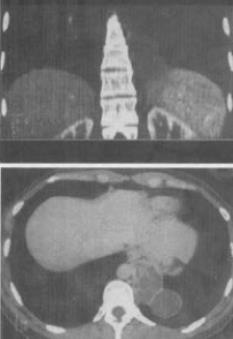

患者男,18岁,无明显症状,体检行CT检查如图,最可能的诊断为()。

A、左下肺膈疝

B、左下肺肺隔离症

C、左下肺癌

D、神经纤维瘤

E、左下肺肺炎

B